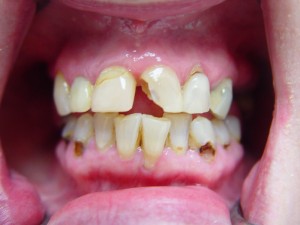

Even with perfect care of your teeth there is always going to be slow deterioration of your teeth. Friction, wear and tear, stress, and corrosion (or any combination of these actions) can cause erosion of the tooth surface and enamel.

All of these actions can cause the need for dental implants, dental veneers, or other dental procedures to help preserve your smile. Obamacare and other government insurance programs that getting these dental procedures done are not cosmetic and not required, therefore they are not covered.